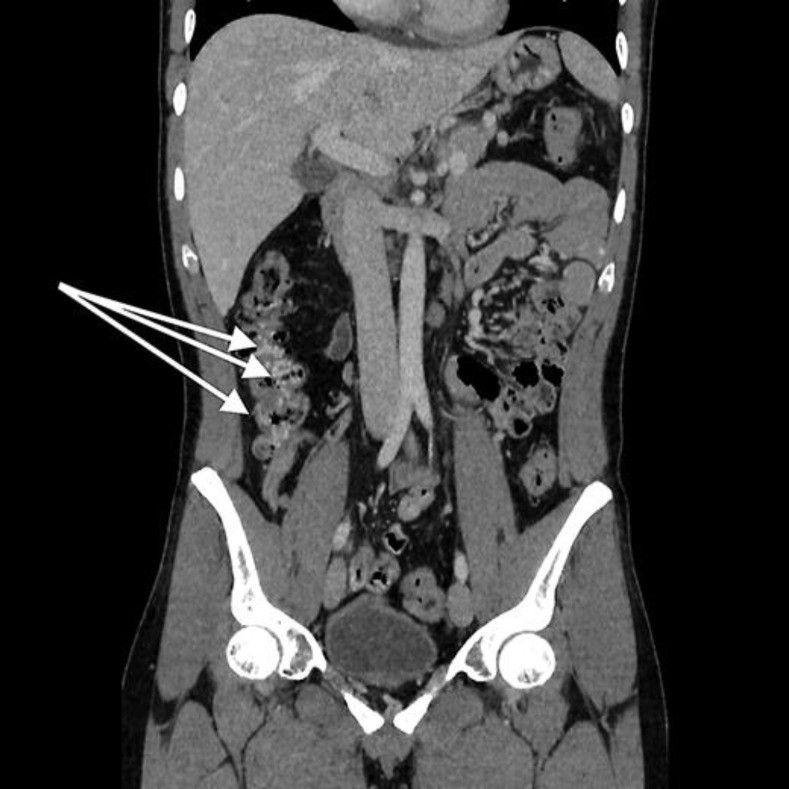

Гастродуоденоскопия с максимальным осмотром двенадцатиперстной кишки ничего не выявила. При компьютерной томографии с болюсным усилением признаков портальной гипертензиии и тромбозов в селезеночной вене не обнаружено, но были очевидны варикозные изменения в ветвях верхней брыжеечной вены в левой эпи- и мезогастральной областях. Обнаружены также признаки варикозного расширения вен в стенке тощей кишки (рис. 1), подвздошной кишке (рис. 2) и ободочной кишке (рис. 3).

Рисунок 2 [1].